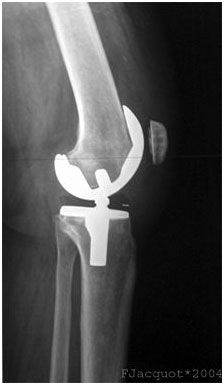

X-ray of total knee replacement, lateral (side) view.